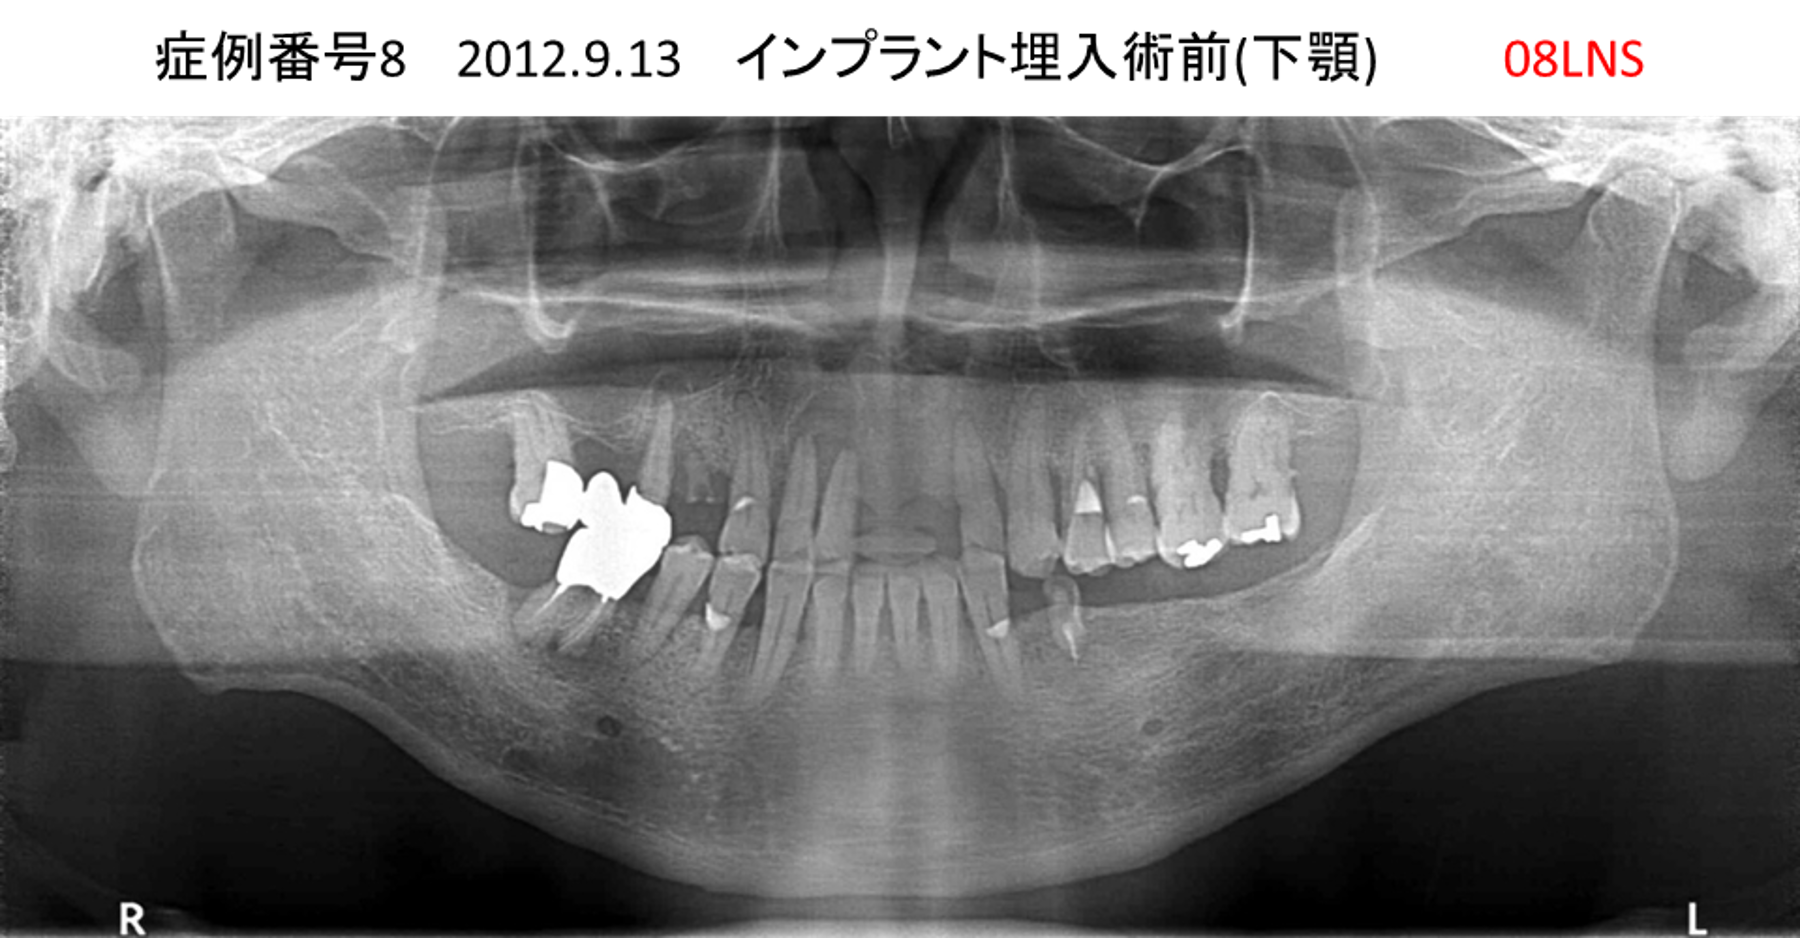

左下の奥歯が痛い患者様のインプラント症例

| 治療名称 |

インプラント |

| 治療費用 |

215万円+税 |

| 治療期間 |

5か月 |

| 患者さんの症状(主訴) |

左下の奥歯が痛い。 |

| 治療内容 |

| 治療結果 |

痛み無く、噛める。 |

| 治療の注意点(リスク/副作用) |

インプラントが壊れたら再治療が必要 |